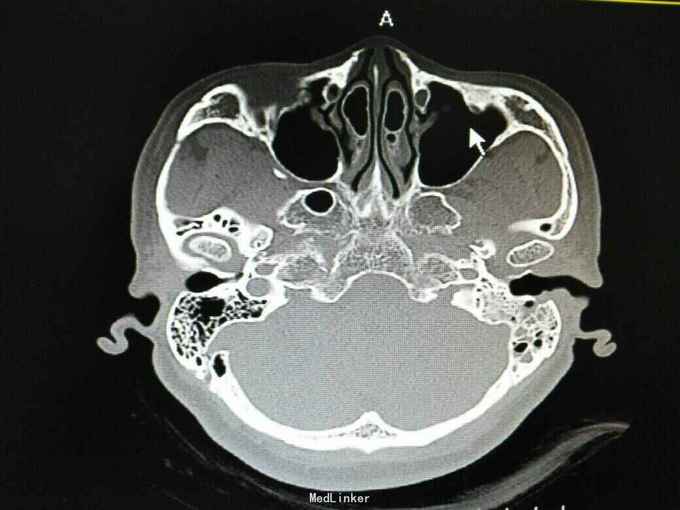

外耳道胆脂瘤,并 分泌性中耳炎? 胆固醇肉芽肿?

患者女性,47岁,以听力下降一周为主诉入院。 就诊后见外耳道后壁缺损,鼓室內积液,给予抗炎治疗后,鼓室內积液由缺损外耳道排出,呈棕褐色。 辅助检查:纯音听阈基本无听力损失。 诊断 外耳道胆脂瘤,并 分泌性中耳炎? 胆固醇肉芽肿? 治疗: 1.乳突根治术?乳突蜂房气化非常好,比较难做。 2.外耳道成型、后壁修补?